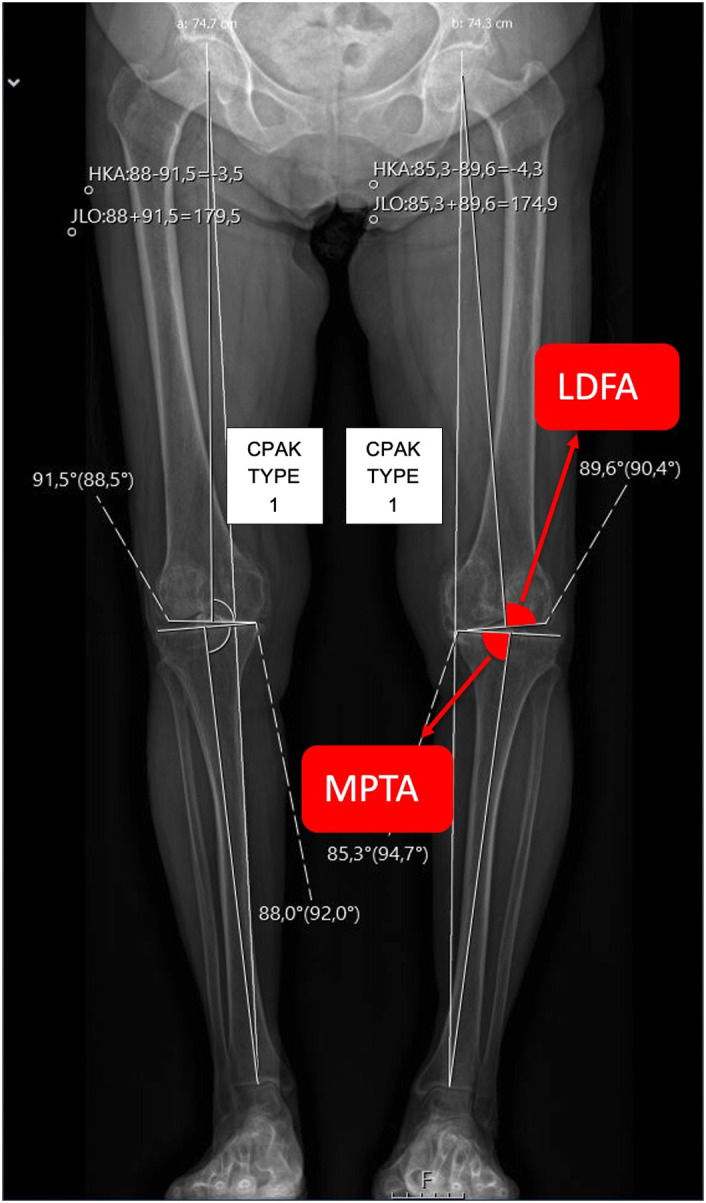

Methods: Radiological EOS analysis of nonarthritic 1172 knees and osteoarthritic 571 knees was evaluated to clarify the distribution of CPAK classification. The knees were categorized into 9 subgroups according to the arithmetic hip-knee-ankle (aHKA) angle and joint-line obliquity (JLO). The medial proximal tibial angle (MPTA) and lateral distal femoral angle (LDFA) were used to calculate aHKA and JLO. The Sectra workstation program was used for all radiological measurements.